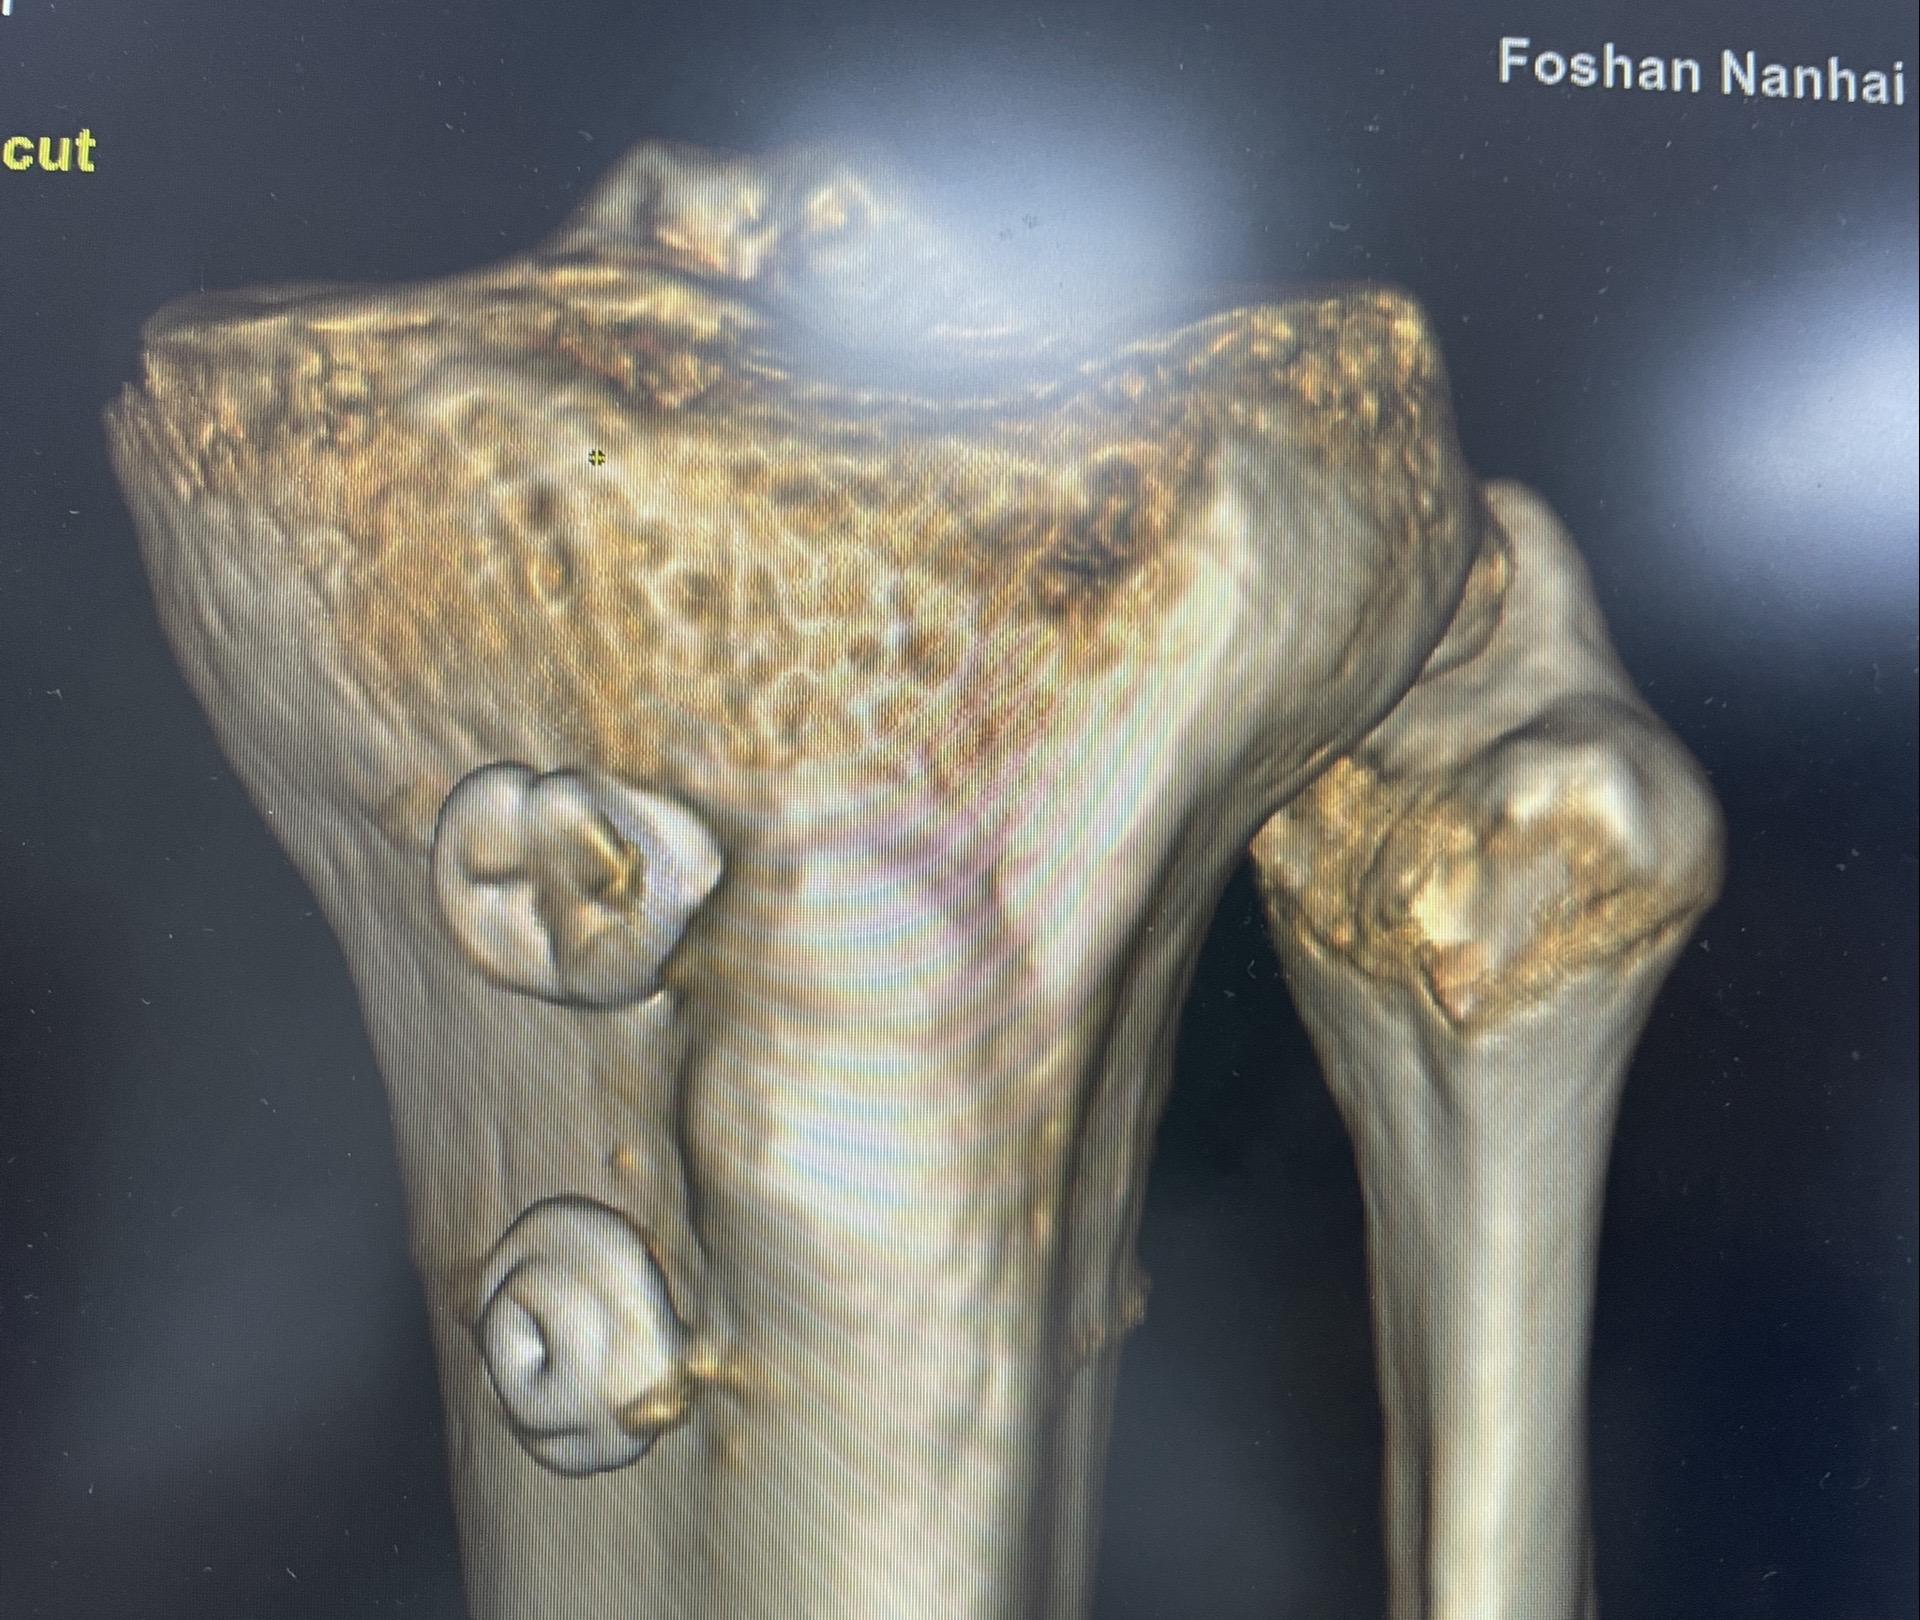

前交叉韧带重建。面对前交叉韧带的断裂,我们选择重建。希望这根强大的移植体,能为他撑起一片天,让他再次在运动场上放飞自我。前交叉韧带重建 前交叉